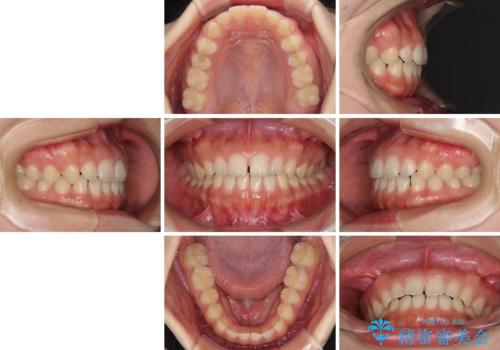

- 後戻りによる上下前歯の隙間を気にして来院された患者様です。

歯列不正はそれほど大きくなかったため、インビザライン・ライトを用いて矯正治療を行うこととしました。

無理のないペースで治療を進め、9ヶ月で終えることができました。